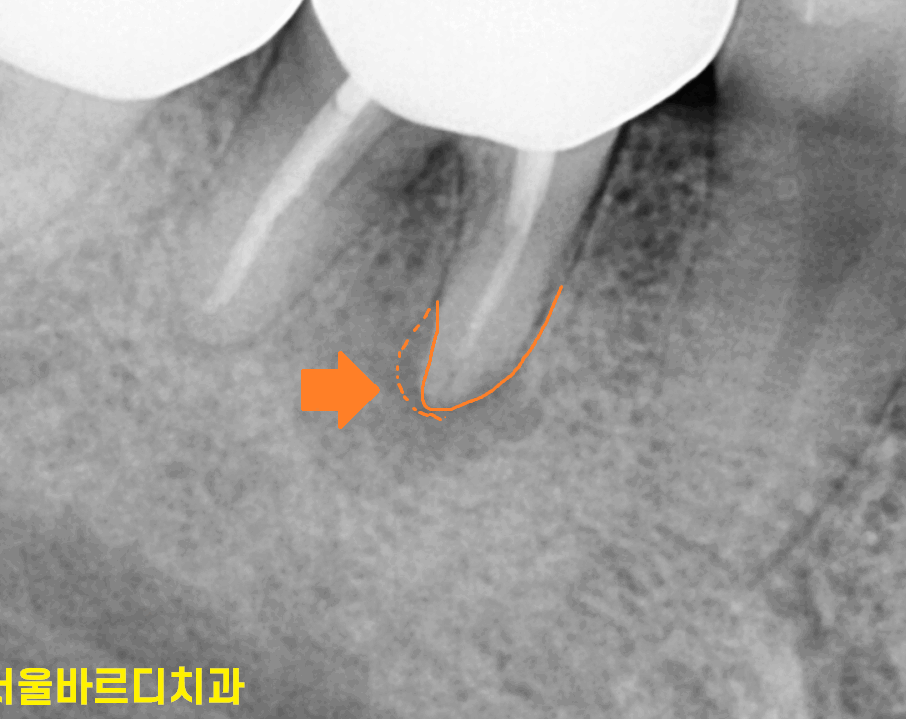

환자분께 말씀드려서 엑스레이를 찍어 보았어요.

230516

역시나 치아 뿌리 끝 염증으로

주변 뼈가 녹은게 관찰됩니다.

염증이 커지면 물혹처럼 잇몸이 부풀어오르셨네요.

그냥 잇몸 물집이 생겼을 리가 없습니다.

염증 지독한 것이

뿌리 모양까지 변화시켰네요.

이전 사진에 비하여 약간 짧아진 게

뿌리까지 흡수되었습니다.